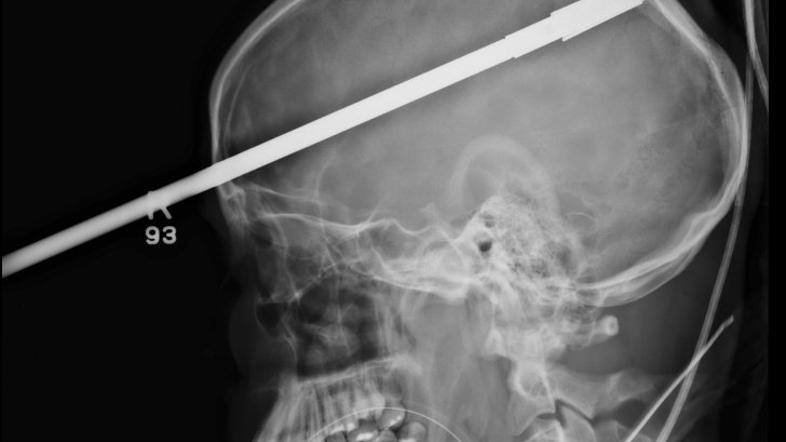

Glavo mu je preluknjala harpuna

Šestnajstletnik čudežno preživel strel v glavo s harpuno. Posledic ne bo imel.

Ribarjenje bi se za 16-letnega Yasserja Lopeza s Floride skoraj končalo tragično. S prijateljem se je odpravil na ribolov, in ko sta pospravljala opremo, se je po nesreči sprožila harpuna.

Harpuna je Yasserja zadela tik nad desnim očesom in na drugi strani glave pogledala ven. Čudežno ni zadela nobenega od pomembnejših možganskih centrov, zato Yasser ne bo čutil nobenih posledic.

Trenutno okreva v bolnišnici v Miamiju. Po besedah osebja pa je bil, ko so ga pripeljali, pri zavesti in je celo komuniciral z njimi. Operacija je trajala kar tri ure, po njej pa se je Yasser že zbudil in spregovoril nekaj besed.

Nesreče se ne spominja.